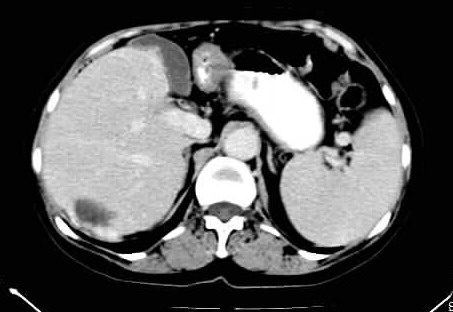

标题: CT24035:肝内占位

肝右叶后段低密度块影,增强后造影剂逐渐向病灶充填,支持肝血管瘤。

右叶后段血管瘤,层面少,看不见左叶,脾大。

肝右叶后段血管瘤、肝左叶缺如、脾大